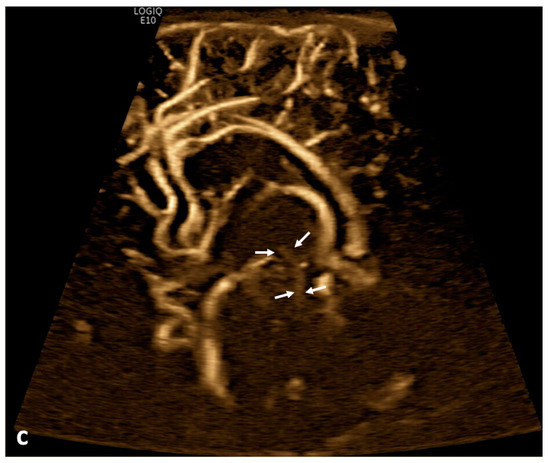

Twenty patients (19.8%) demonstrated apparent CSF flow detectable using MVI in at least one of the ventricular structures: 11 (10.9%) in the third ventricle, 16 (15.8%) in the cerebral aqueduct, and 17 (16.8%) in the fourth ventricle (Figure 1 and Figure 2). Of these 20 patients, 13 had IVH as visualized in grayscale US; flow direction was detected as craniocaudal in 15% (n = 3) of patients, caudocranial in 70% (n = 14), and bidirectional in 15% (n = 3) (Supplemental S1 and S2; Table 1). The IRR for detection of CSF flow was 0.662, p < 0.001.

Figure 2.

Cerebrospinal fluid (CSF) flow visualized in a patient with post-hemorrhagic hydrocephalus. A 7-day-old boy with a history of severe intraventricular hemorrhage and ventriculomegaly. Coronal and sagittal grayscale ultrasound shows enlargement in the lateral and third ventricles, as well as evolving choroid plexus hemorrhage and fine granular mobile debris in the ventricles (a–c). The parenchymal evaluation shows grade IV left parieto-occipital periventricular hemorrhage (c). Sagittal B-Flow (d–f) demonstrates turbulent caudocranial CSF flow from the cerebral aqueduct (arrows) into the third ventricle (dotted arrows). The entire clip is provided as Supplemental Material S2.